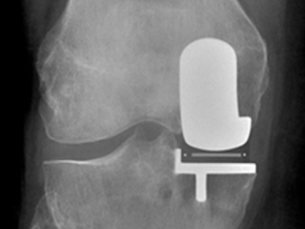

Stiffness after total knee replacement - how to avoid it and treat it!

Approach to a Patient with Stiffness After Total Knee Replacement (TKR) Stiffness following total knee replacement can pose significant...